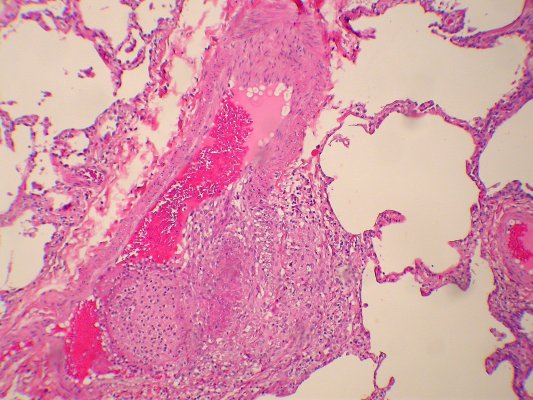

Микроскопический взгляд на мишитарный туберкулез легкого: фотодокументация

Раздел: Снимки-откровения